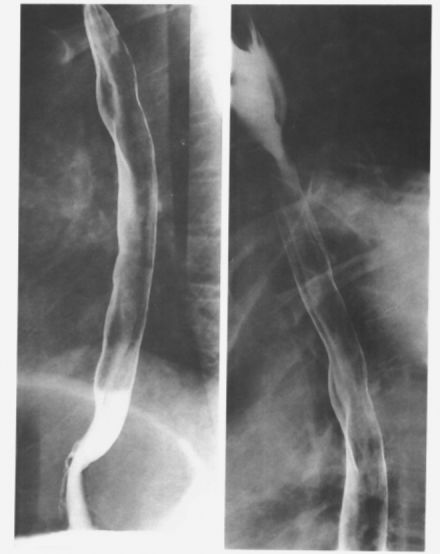

食管静脉曲张:蚯蚓样、串珠状。

食管重度静脉曲张

食管静脉曲张:食管黏膜呈现蚯蚓状

这是食管静脉曲张伴胃底静脉曲张的图像